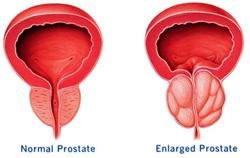

Prostate enlargement (also known as benign prostatic hyperplasia or benign prostatic hypertrophy) is a common condition that usually affects men at about 50 years of age and above.

Prostate enlargement (also known as benign prostatic hyperplasia or benign prostatic hypertrophy) is a common condition that usually affects men at about 50 years of age and above.The enlarged gland squeezes the urethra, causing problems in urinating. The initial symptom is a frequent and urgent need for urination, especially at night. Other symptoms include difficulty starting urination, difficulty emptying the bladder fully and blood in the urine (haematuria). In the presence of cold, tiredness or after consumption of alcohol, both the prostate and the neck of the urinary bladder may become engorged and edematous leading to further blockage. In late stages, prostate enlargement can result in urine retention and cause complications like bladder stones, bladder infections and damage to the kidneys.

The cause of this condition is not clearly understood. One theory suggests that it is caused by the abnormal increase in dihydrotestosterone (DHT); another theory suggests that it is related to a decrease in testosterone levels, causing a relatively higher proportion of oestrogen in the body. The change in hormone levels due to ageing may stimulate the growth of the prostate.

Acupuncture and Chinese herbal medicine are used in an effort to regulate the secretion of sex hormones to achieve a proper balance. In addition to improving local circulation, the treatment also aims to suppress the proliferation of fibrous tissue, decrease inflammation and control exudation, resulting in a decrease in the rate of enlargement of the prostate. It reverses engorgement and edema of the ureter and improves micturition.